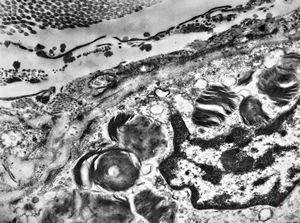

F, 24y. | molluscum contagiosum … virions

F, 24y. | molluscum contagiosum

F, 7y. | molluscum contagiosum … virions